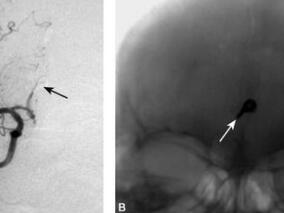

1小时条评论1 病例简介 例1 患者女,11岁,主因阵发性头痛9年,加重10天于2009年6月15日收入院。患者9年前无明显诱因出现头痛,为右额颞部钝痛,持续1~2小时后缓解,之后每年发作4~5次。10日前再次头痛发作,伴左侧肢体无力,到当地医院就诊,CT示右侧额颞占位,考虑动脉瘤...

1小时条评论1 病例简介 患者男,40岁。主因突发头痛、呕吐42小时于2009年11月2日入院。患者于入院前42小时在活动中突发剧烈头痛伴有恶心呕吐。到当地医院就诊,CT示蛛网膜下腔出血(图4.3-1)。为进一步诊治到我院就诊。急诊DSA示前交通动脉瘤(图4.3-2),立即给予血管内动脉...